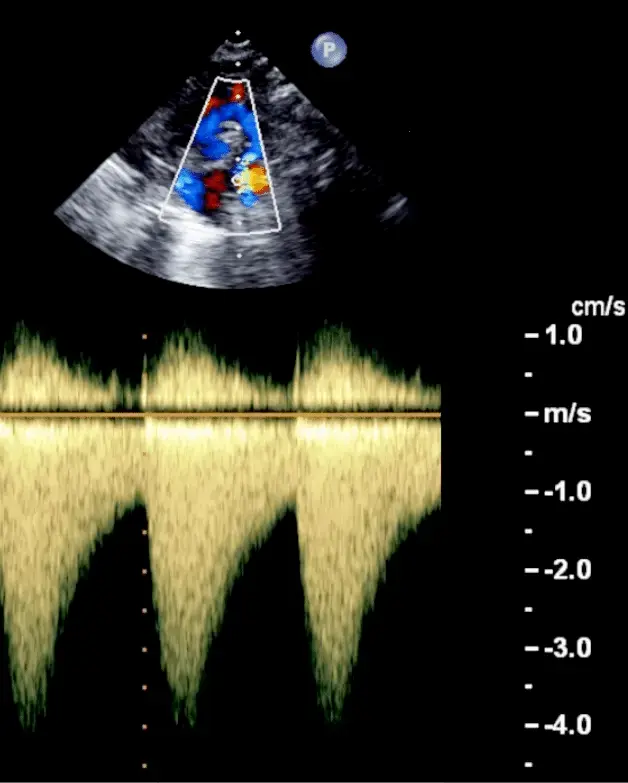

Echo for Valvular AS

- Cannot tell severity of stenosis with 2D-echo alone. You will need Doppler to help determine severity of AS.

- Aortic velocity is measured using continuous-wave doppler ultrasound with examination from multiple acoustic windows

Underestimation due to improper Doppler alignment across the Aortic Valve

If not parallel to the AS jet, you will not get the highest mean AV gradient or peak velocity across the AV → underestimate severity of AS. Importantly, you cannot overestimate the gradient (Exceptions: significant anemia or Subaortic Stenosis).

- Doppler assessment

- Measurements required

- LVOT diameter (2D)

- LVOT velocity, TVI (PW Doppler)

- Peak AV velocity, TVI (CW Doppler)

- Aortic valve area (AVA)

- Continuity equation valve area:

- Requires 3 measurements:

- AS jet velocity (CW Doppler),

- LVOT diameter to calculate cross-sectional area (CSA), and

- LVOT velocity (PW Doppler)

- The above figure is from the Mayo Echo Boards video where the presenter highlights the importance of calculating the AV TVI in multiple windows to ensure you are appropriately calculating the highest VTI and avoid miscalculation/miscalssification. In Thaden et al (JASE, 2015), the authors found that peak velocity was found outside of the apical window 61% of the time and that neglecting non-apical window misclassified AS 23% of the time.